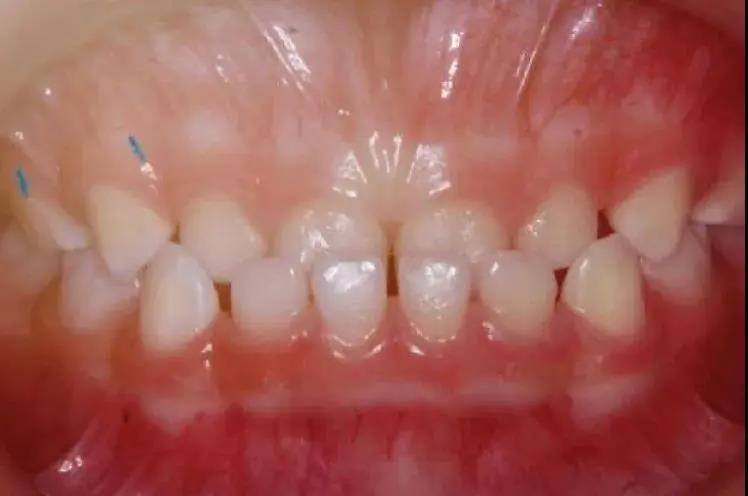

例如孩子在咀嚼的時候

上門牙咬在下門牙的后方

(俗稱“地包天”)

如果不做早期矯治

會直接影響孩子面型及頜骨發(fā)育